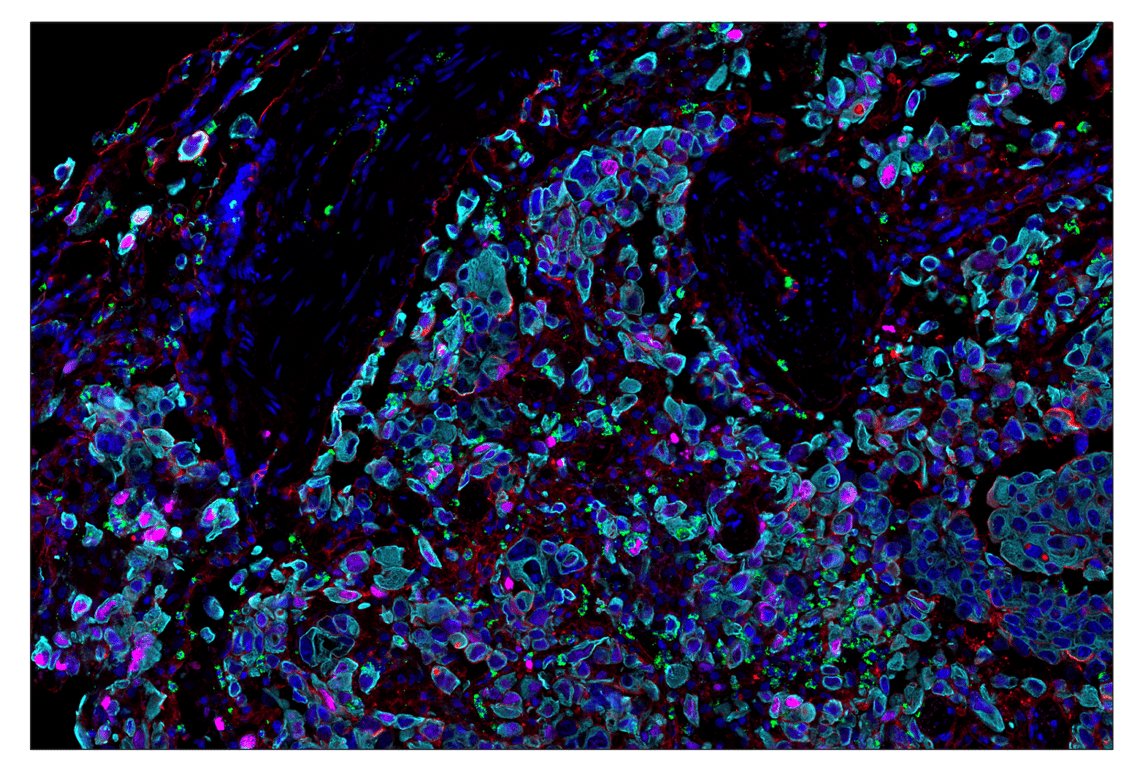

SignalStar™ multiplex immunohistochemical analysis of paraffin-embedded human tonsil using Phospho-Histone H2A.X (Ser139) (D7T2V) & CO-0135-488 SignalStar™ Oligo-Antibody Pair #66478 (magenta), CD54/ICAM-1 (E3Q9N) & CO-0146-594 SignalStar™ Oligo-Antibody Pair #32147 (yellow), Myeloperoxidase (E1E7I) & CO-0138-647 SignalStar™ Oligo-Antibody Pair #53259 (red), Pan-Keratin (C11) & CO-0003-750 SignalStar™ Oligo-Antibody Pair #97227 (cyan), CD8α (D8A8Y) & CO-0004-488 SignalStar™ Oligo-Antibody Pair #45747 (green), Ki-67 (8D5) & CO-0014-594 SignalStar™ Oligo-Antibody Pair #35330 (white), and α-Smooth Muscle Actin (D4K9N) & CO-0024-647 SignalStar™ Oligo-Antibody Pair #63902 (orange). All fluorophores have been assigned a pseudocolor, as indicated. Staining was performed on the BOND RX autostainer by Leica Biosystems.

Immunohistochemistry Image 1: Myeloperoxidase (E1E7I) & CO-0138-750 SignalStar<sup>™</sup> Oligo-Antibody Pair